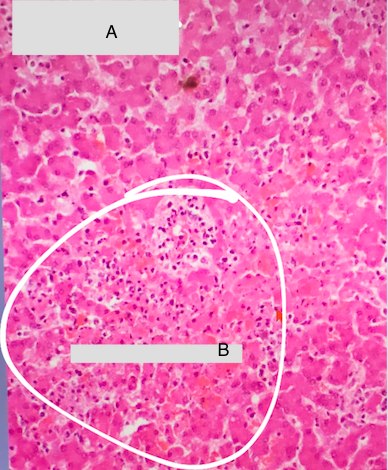

Label this photo